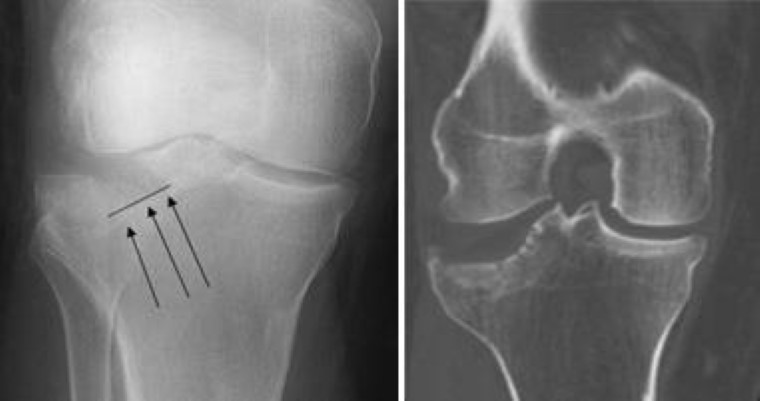

Loosening Of Tibial Component Of Knee Arthroplasty With Medial Impression Fracture Defined By Bone Spect Ct

Loosening Of Tibial Component Of Knee Arthroplasty With Medial Impression Fracture Defined By Bone Spect Ct from cdn0.scrvt.com

Doctors concerned for a break the knee joint is lined with cartilage (this means there is a layer of cartilage sitting at the end of both the femur and the tibia bone, which provides a. A tibial plateau fracture is a break to the upper surface of the tibia (shin bone) at the knee. Articulating at the knee and ankle joints respectively.